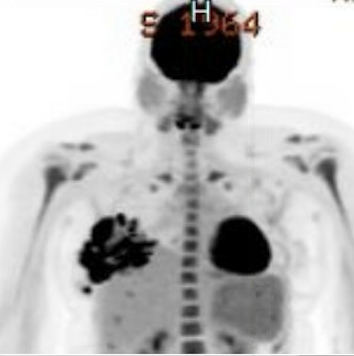

Lactating Adenoma

Lactating adenomas are benign (non-cancerous) masses comprised of dense glandular tissue and most commonly occur in the upper outer part of the breast. They can present during pregnancy or lactation and likely are related to hormonal stimulation. They may become large; however, they reduce in size as a woman progresses further in the postpartum period and eventually disappear when lactation is complete. They can appear similar to fibroadenoma on breast imaging, as smooth, oval lesions. Diagnosis can be confirmed with a core needle biopsy, but they do not require surgical excision.